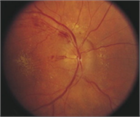

1. 血圧は両上肢で測定し左右差を確認する。眼底所見は高血圧緊急症の診断に有用であるため、確認すべきである(推奨度2)